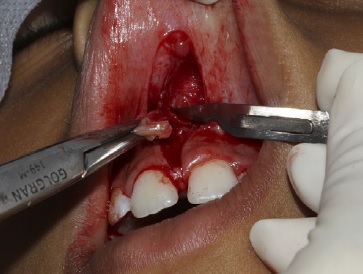

Em seguida, foi realizado o pinçamento na posição apical do freio com a pinça hemostática Kelly e foram efetuadas duas incisões verticais com lâmina de bisturi n.º 15c (Solidor, Brasil) em forma de “v”, com incisão no fundo de sulco até a região da papila interincisiva para a remoção do freio labial superior em nível supra periosteal (Figura 2‑3-4-5).

Essa papila interincisiva foi preservada para não provocar um espaço negro (black space). Após a remoção do tecido fibroso entre o segmento interdental e a papila interincisiva na região palatina, foi realizado um debridamento com gaze (Cremer, Brasil), ou seja, uma fenestração óssea (Figura 6), fazendo uma pequena fricção entre os dentes para remover as fibras mais internas que estavam em contato com o osso. Em seguida, foi feito a divulsão dos bordos, isto é, um descolamento do tecido mucoso em relação ao tecido muscular e remoção de fibras que se encontravam unidas ao osso. Esse procedimento foi feito com a pinça Dietrich para pinçamento dos bordos, inserção da tesoura sempre fechada dentro do tecido e só era aberta dentro do plano mucoso, fazendo a divulsão dos tecidos. Foram encontradas algumas glândulas salivares menores e estas foram removidas.